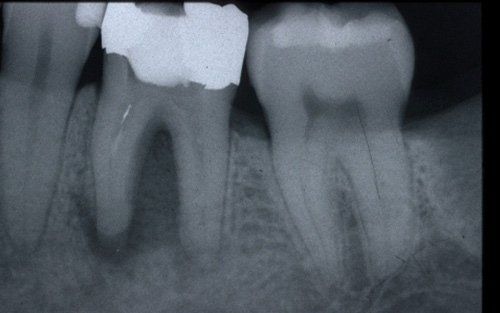

Endodontics, or root canal therapy, is that branch of dentistry that deals with the

devitalisation of teeth.

This treatment should be reserved for teeth that have irreversible pulp pathology (the nerve of the tooth) or an infection of the dental canals that has caused an abscess (acute apical periodontitis) or a granuloma (chronic apical periodontitis). While in the first two cases the tooth is very painful and the patient immediately seeks the dentist, the case of the chronic form is often silent, and therefore the patient may not notice anything for a medium to long period of time. In such conditions, it is only an X-ray image, taken during routine check-ups, that detects its presence. Root canal therapy can be completed by placing a latest-generation post inside the canal, as a means of retaining the material used for the reconstruction of the tooth. It will be up to the clinician to decide whether or not the restoration requires this additional anchoring system.